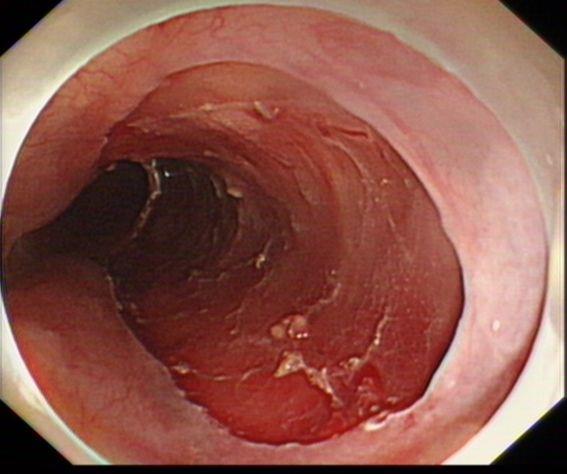

完整剥离病灶

术后标本卢戈碘染示:病灶完整剥离

术后病理示:食管黏膜高级别上皮内瘤变